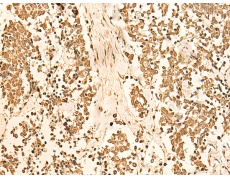

IHC positive control:

Human breast cancer and Human lung cancer

IHC Recommend dilution:

50-300